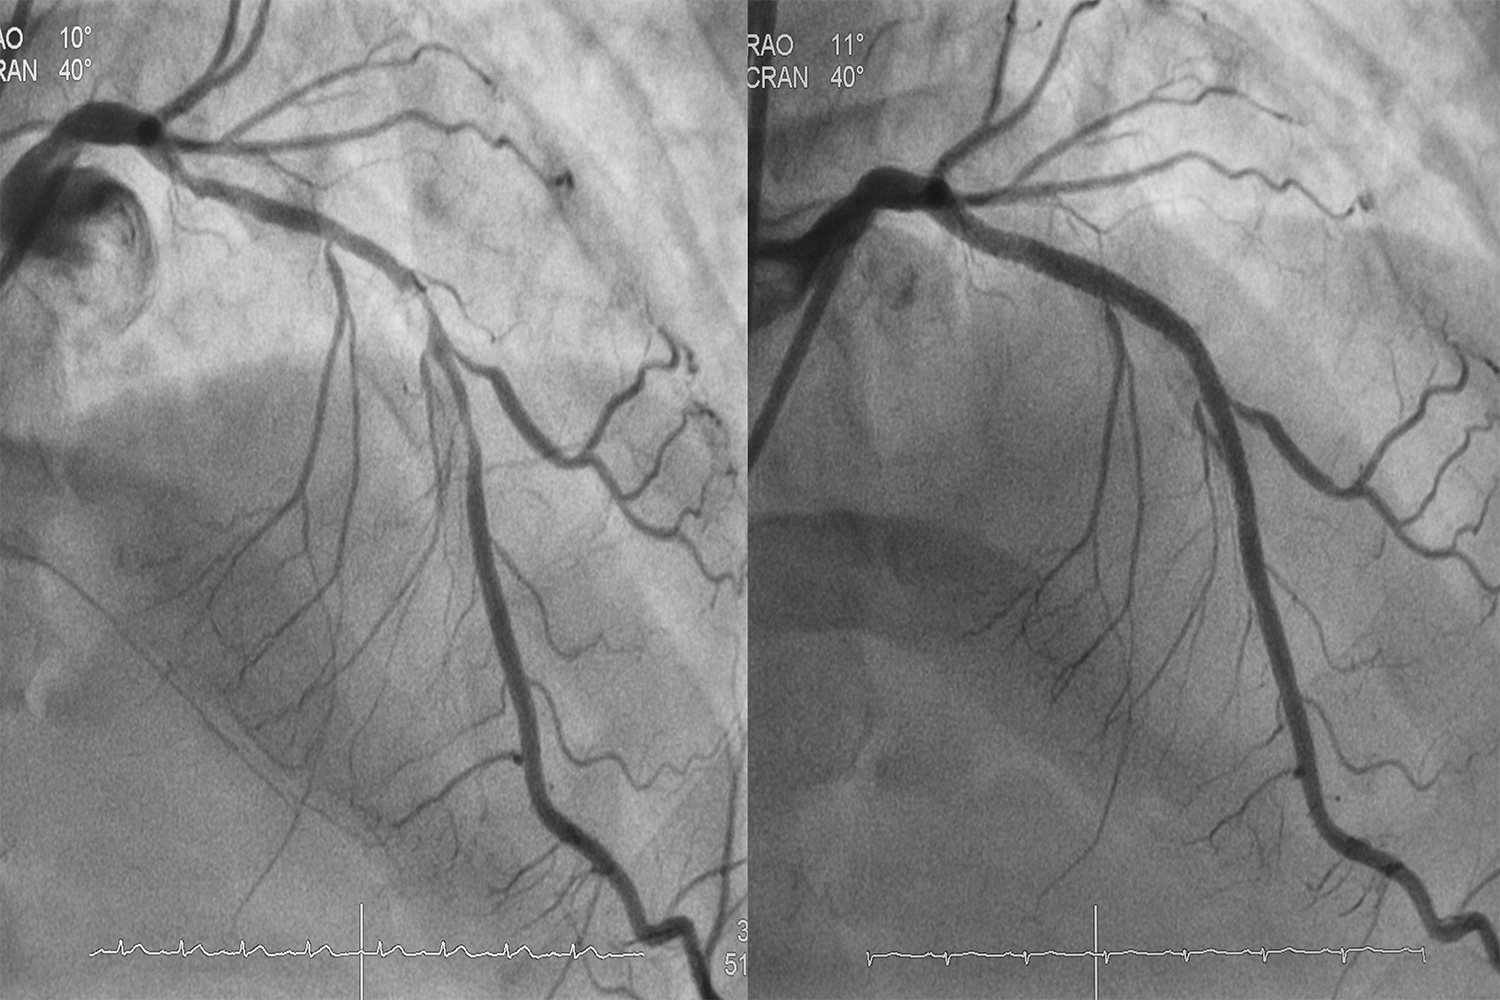

Herzkatheter

Herzkatheter-untersuchung

Abklärung und Behandlung von Durchblutungsstörungen der Herzkranzgefäße mit modernsten Methoden.

Über die Arterie am Handgelenk werden die Herzkranzgefäße dargestellt und Engstellen bei Bedarf sofort mit Stents behandelt.